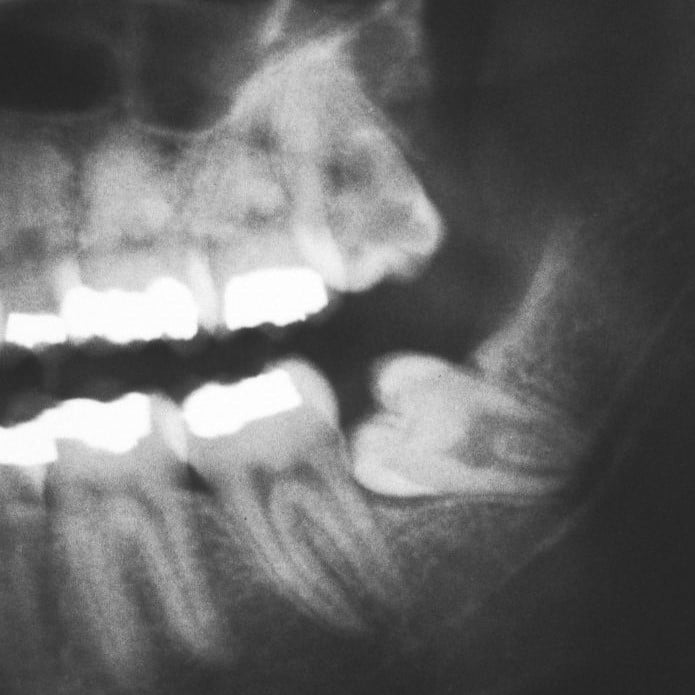

엑스레이 상에서 본 사랑니의 모습입니다. 아예 사랑니가 누워있죠... 이 경우 염증이 일시적으로 사라졌다가도 다시 재발하는 경우가 흔합니다. 발치를 통해 근본적인 원인을 제거하시는걸 추천드려요 (출처: https://wesmiledental.sg/)

특히

염증이 반복되거나

고름까지 동반된 경우라면

발치를 통해 근본 원인을 제거하는 게 더 안전한 선택일 수 있어요.